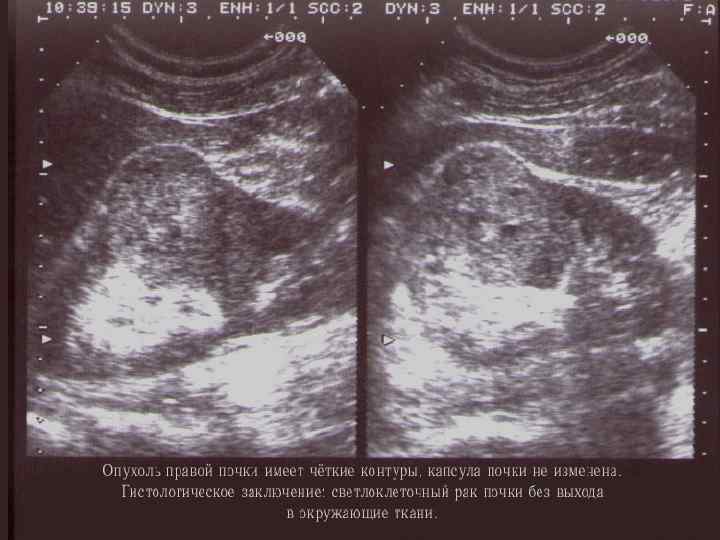

УЛЬТРАЗВУКОВОЕ ИССЛЕДОВАНИЕ

ДИАГНОСТИКА § Лабораторная диагностика «паранеопластического» синдрома (ОАК, СОЭ) и ОАМ (60 -75% гематурия); § КТ высокого разрешения с контрастом → определении стадии TNM; § в/венная урография – для определения анатомии и функции контрлатеральной почки; § УЗИ брюшной полости; § МРТ при подозрении на опухолевый тромбоз НПВ, ХПН или аллергии на в/венный контраст; § Рентгенография грудной клетки → MTS? .